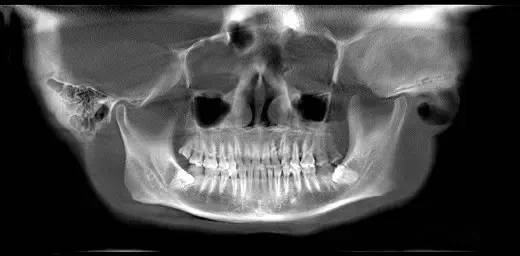

第二圖:上頜竇氣化,導(dǎo)致上頜竇很大,骨高度不足,但是上頜竇底平,粘膜很干凈。適合外提升或者高手可行內(nèi)提升。(還有二次內(nèi)提升)。